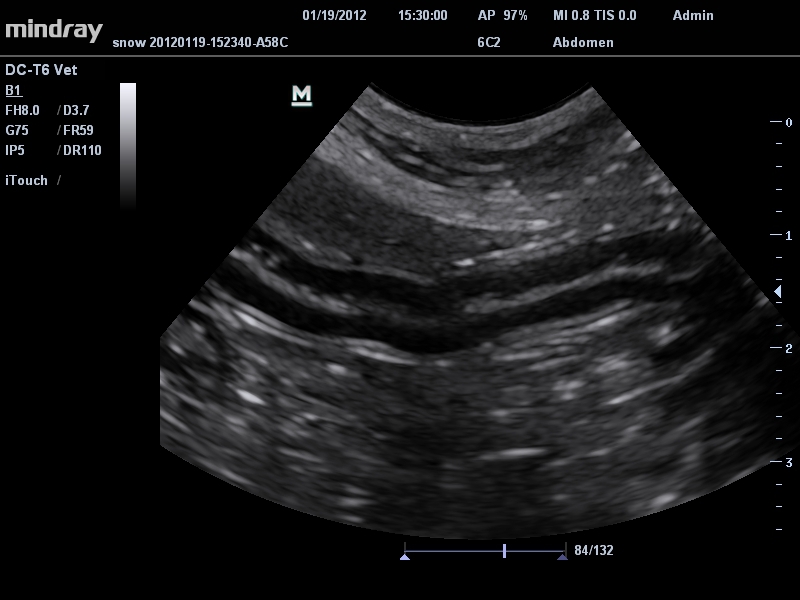

• Микроконвексный датчик Mindray 6C2

Система сочетает в удобном и компактном корпусе не только традиционные возможности современного УЗИ-сканера, но и инновационные технологии, повышающие точности диагностики состояния пациентов.

• Режимы сканирования: B/M/CFM/PDI/Направленный PDI/PW, HPRF, Тканевая гармоника, М- и цветной М-режим.